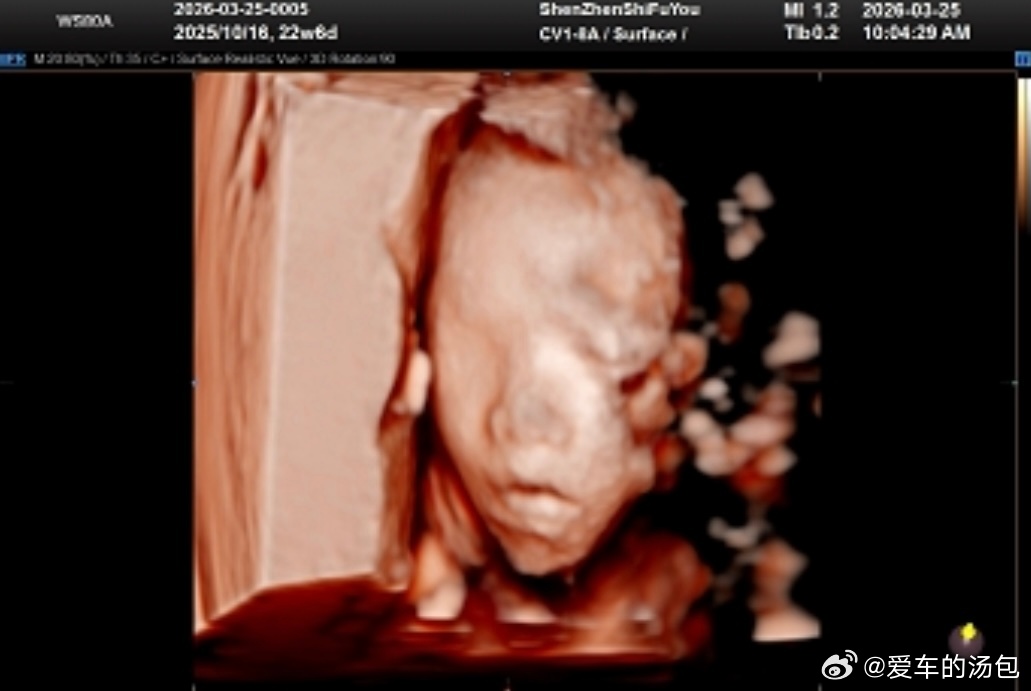

如果幸福是酵母,那我一定是蓬松的面包🥰会像谁呢~我鸿的恋爱日记